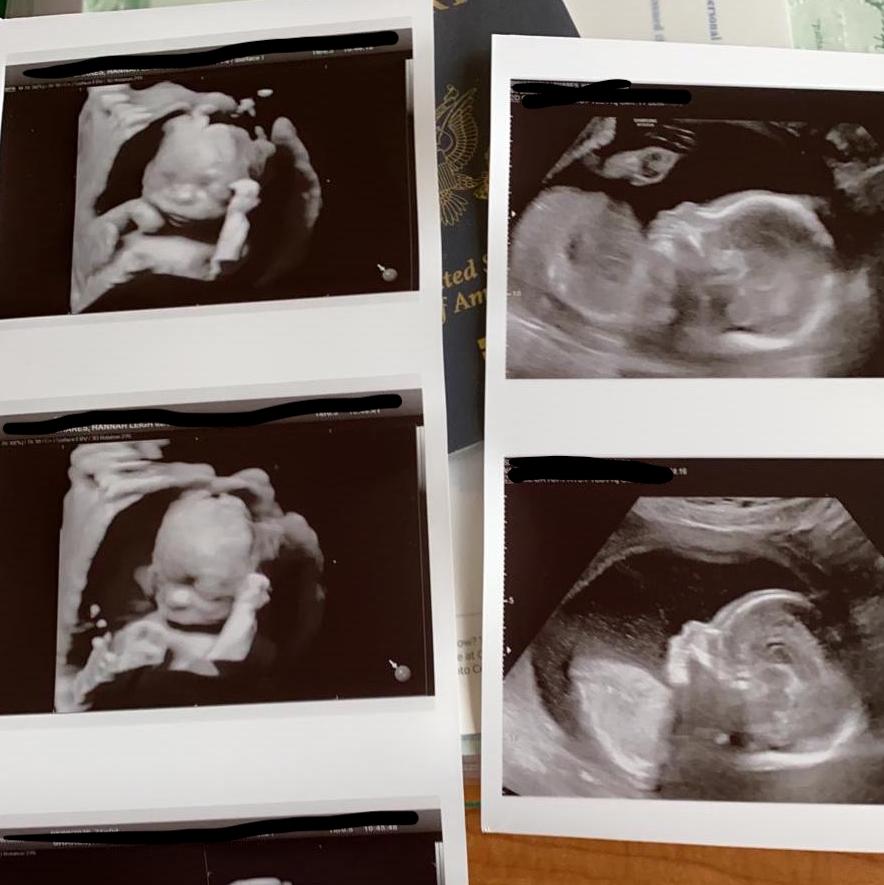

A little update on Baby Shares: I am 21 weeks today and had my first appointment at the Italian hospital this morning. The nurses and my doctor were wonderful and Michael was able to come with me for this appointment since it was the first and it was the anatomy scan. Unless there are changes to the hospital’s policies, he won’t be able to come to any other appointments until the birth. This was my first ultrasound since 10 weeks, and the first time Michael was able to be there! It was so fun to see how much Baby has grown and we even got to see facial images in 3-D. We are choosing not to find out the gender, although Michael was trying to play ultrasound-tech during the scan to figure it out for himself.